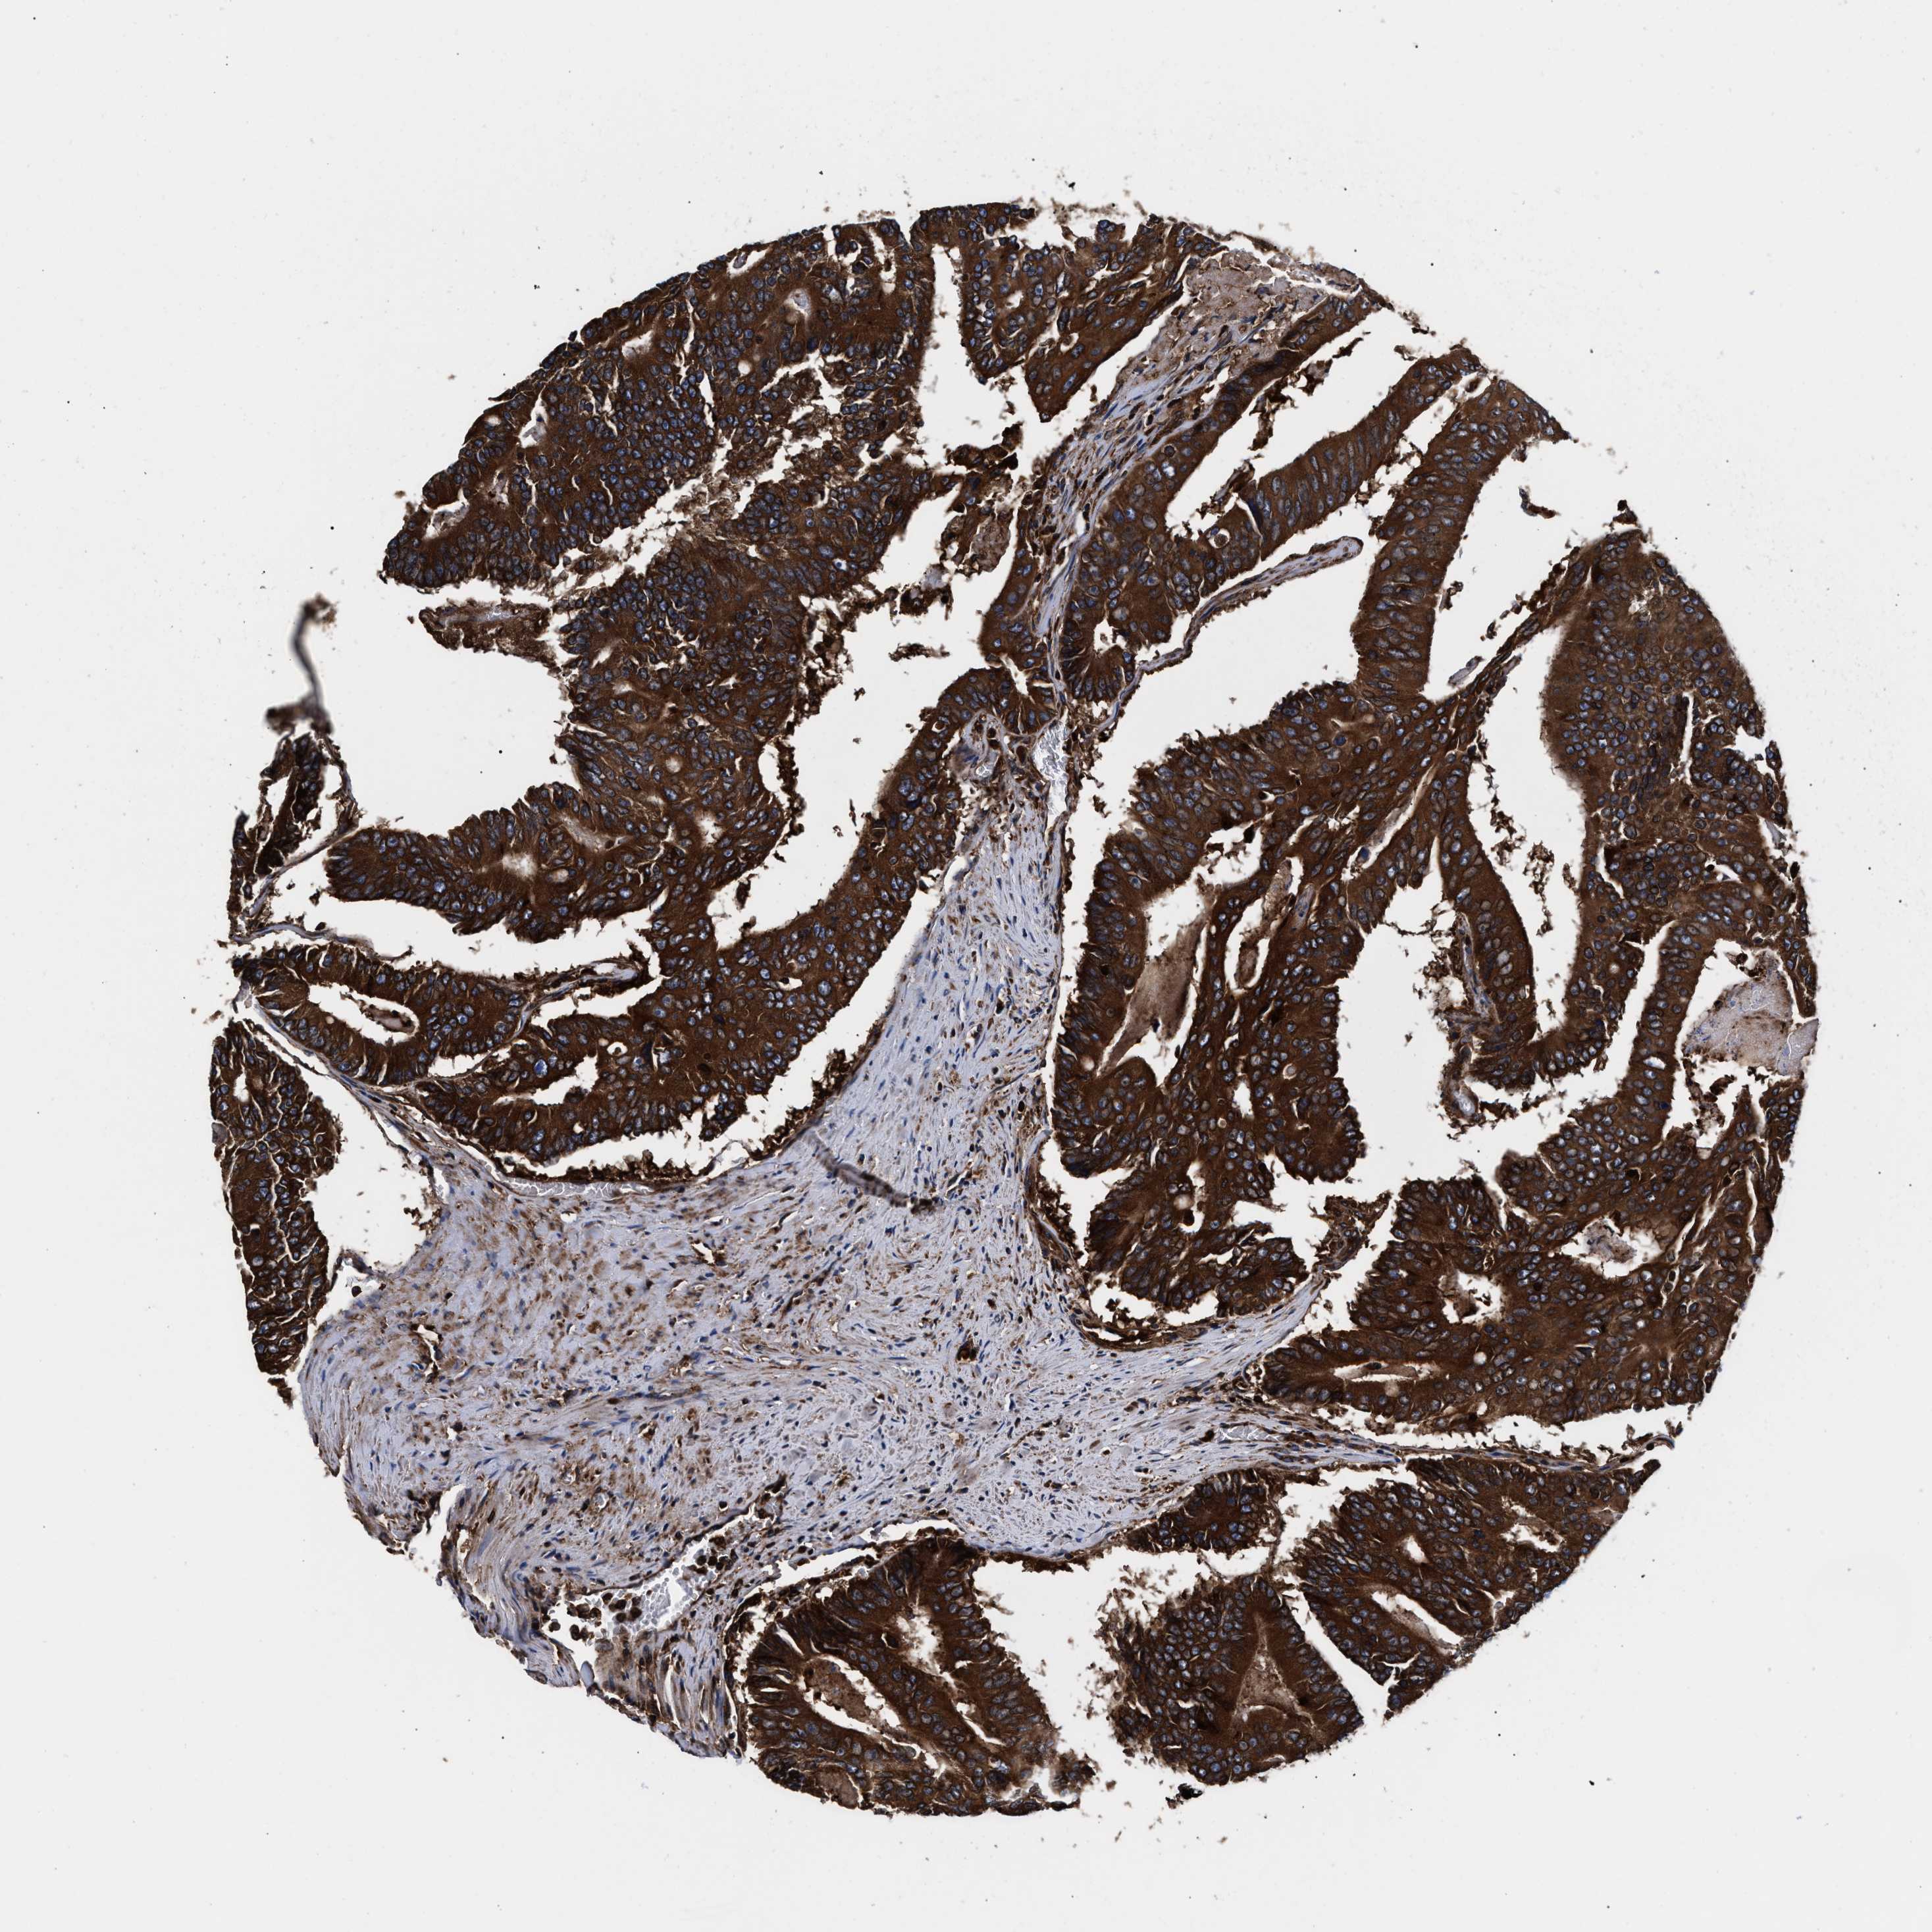

CANCER COLORECTAL CANCER Show tissue menu

Colorectal cancer

Human cancer

Colon adenocarcinoma